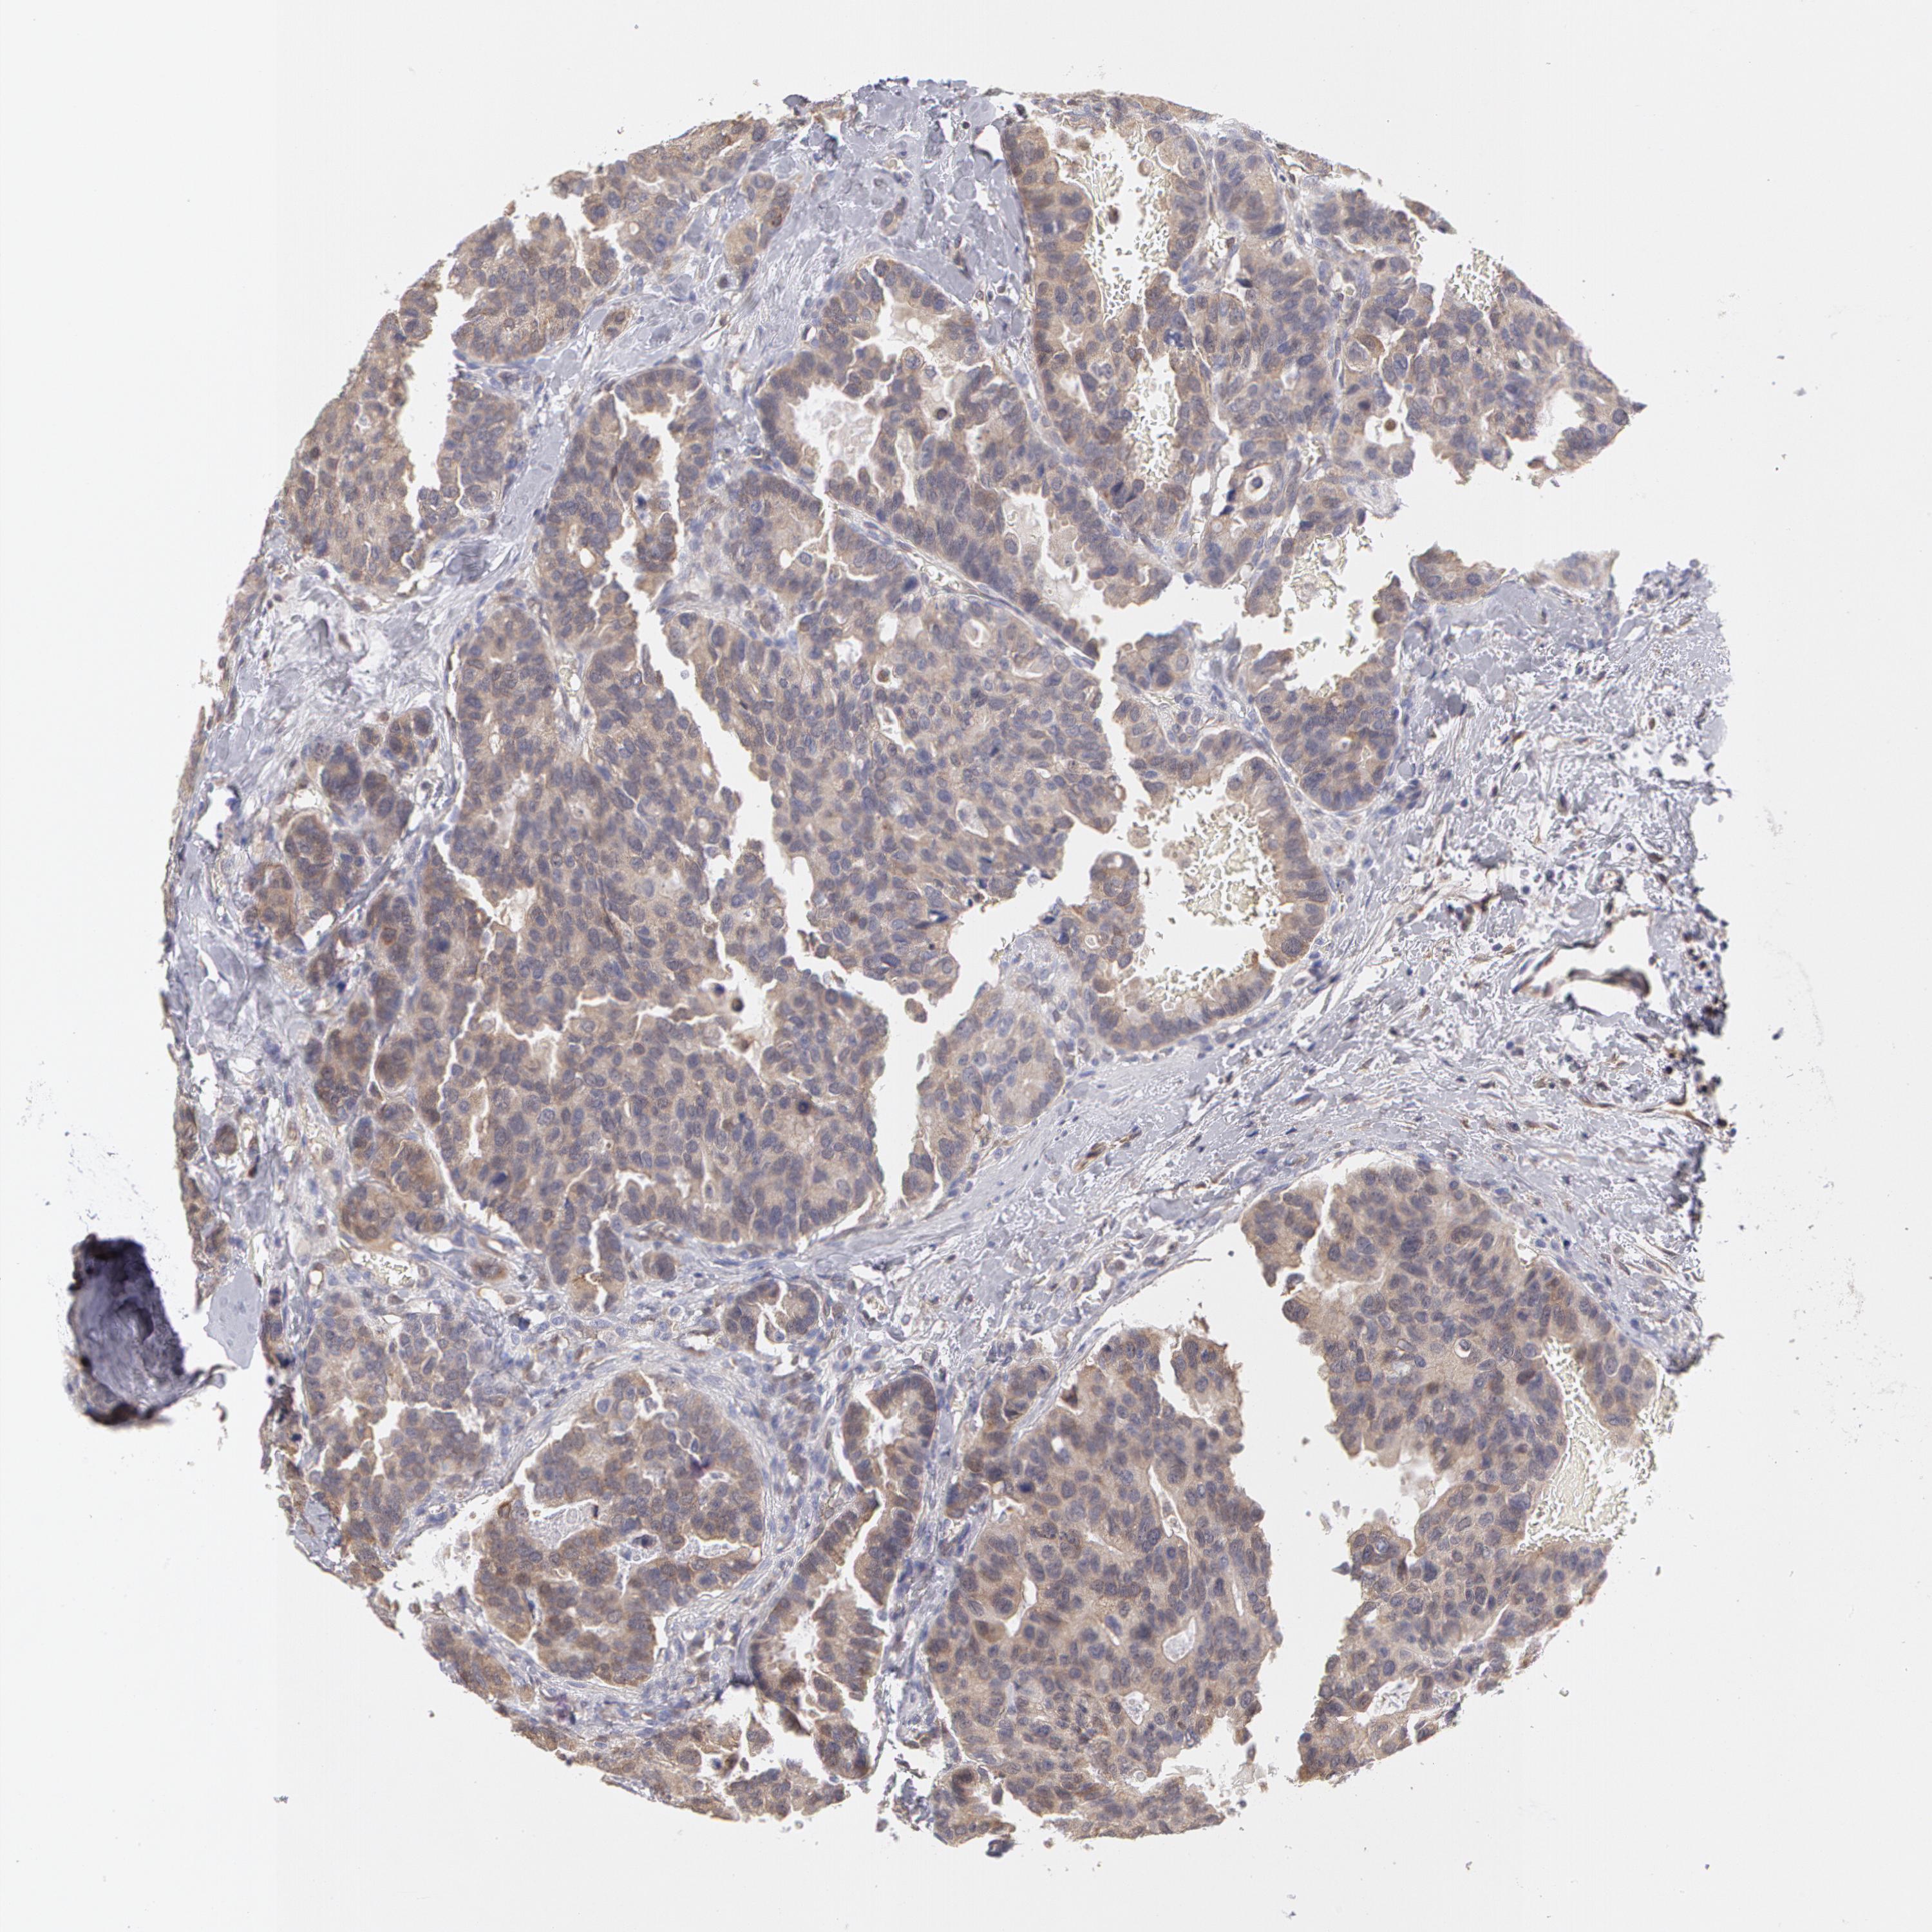

CANCER BREAST CANCER Show tissue menu

BRCA TCGA BRCA VALIDATION PROTEIN EXPRESSION

Breast cancer

Human cancer